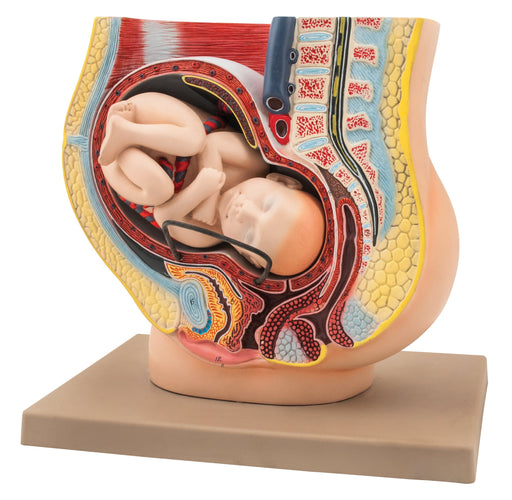

Female Pelvis with Baby, 13 Inch - Shows Pregnancy at 9 Months, Full Term - Removable Fetus - Eisco Labs

REMOVABLE FETUS || 3-dimensional female pelvis model showing the 9th month of pregnancy includes removable fetus MEDIAN CROSS-SECTION || For use ...